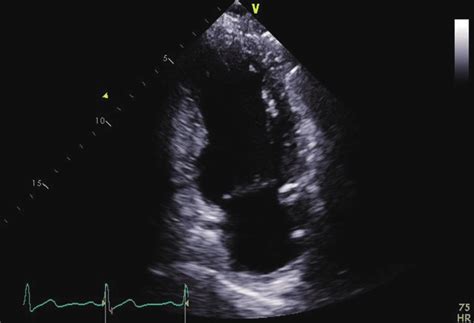

Transthoracic echocardiography of a congenital left ...

Transthoracic echocardiography of a congenital left ... from heart.bmj.com

Right and left coronary cusps of the aortic valve. The coronary sinus is a collection of smaller veins that merge together to form the sinus (or large vessel), which is located along the heart's posterior (rear) surface between the left ventricle and left atrium. From recent mouse studies, the origin of this specialised vasculature is from the sinus venosus. Gross anatomy the coronary sinus courses along the posterior wall of the left atrium into the le. The coronary circulation provides the blood supply to the heart required for the normal muscular function. Total anomalous pulmonary venous return to the coronary sinus. An incidental note of an unroofed coronary sinus (cs) was made on the coronary ct angiogram ( figure 1a through 1 d). Apical four chamber view showing the coronary sinus type total anomalous pulmonary venous connection in a newborn and a secundum asd (atrial septal defect).

The right coronary artery (rca) the coronary artery that supplies the pda (posterior descending coronary artery), which supplies the inferior wall of the left ventricle, determines the. Two horns, right and left, which eventually form the svc, ivc, coronary sinus, and posterior wall of the divide the av canal into two chamber and parts of the mv and tv; On occasion, however, even infants develop clinically important symptoms of congestive heart martin ss, shapiro ep, mukherjee m. Apical four chamber view showing the coronary sinus type total anomalous pulmonary venous connection in a newborn and a secundum asd (atrial septal defect). Dual chamber av sequential pacemaker.